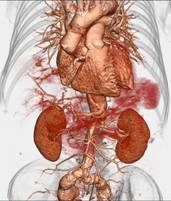

320排螺旋CT具备16cm宽覆盖探测器,实现动态容积扫描,360度的各向同性采集能力及[email protected]%密度分辨率的量子探测器,一次心跳全心脏采集,一圈扫描器官成像,一次检查完成多重任务,实现真正的动态容积体灌注及心脏、神经一站式检查;西门子Flash炫速CT扫描系统,具备两套同时旋转的X射线球管及探测器,实现了43cm/s的极快CT扫描速度和75 ms的时间分辨率,完成全胸扫描仅需0.6秒,使得患者做心脏扫描时无须食用β-受体阻滞药,亦无须屏气,并可实现低于1mSv的超低辐射剂量,配置第二代双能量、宽151级纯化能谱,组织鉴别能力进一步提高,可开展多达10余种双能量成像应用。

※肝脏、胰腺、肾脏CT-DSA 及灌注功能一站式检查